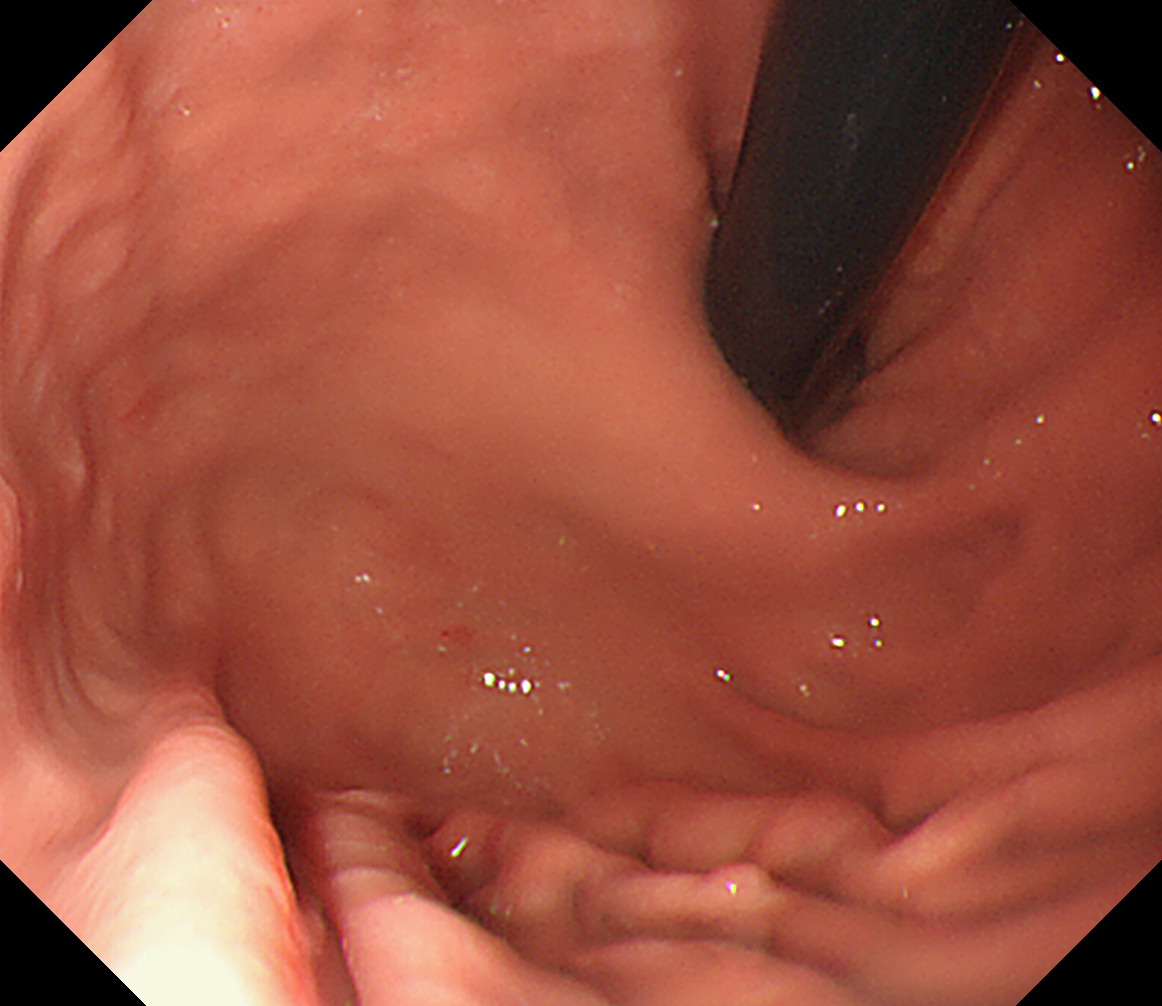

■ 実際の撮影(39ショット)

順番 部位 説明 画像

24 体下部後壁 引き上げて

後壁から反時計回り

接線になり見逃しやすい部位です

体下部後壁